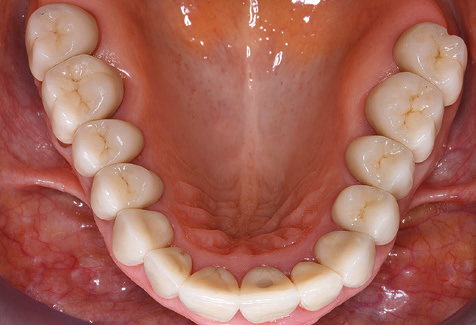

Eine 52-jährige Patientin stellte sich nach Zahnverlust im 3. Quadranten erstmals 2004 vor. Sie hatte den Wunsch nach einer prothetischen Neuversorgung. Im Rahmen der parodontologischen und radiologischen Diagnostik zeigte sich ein ausgeprägter parodontologischer Behandlungsbedarf. Die Zähne 48, 28, 27 zeigten zudem eine infauste Prognose und wurden entfernt (Abb. 1). Nach der erfolgreich abgeschlossenen systematischen PARTherapie wurde eine festsitzende implantatprothetische Versorgung mit Insertion von fünf Implantaten in Regio 35, 36, 37 und 46, 47 durchgeführt. Die prothetische Versorgung der natürlichen Zähne erfolgte mit verblendeten Zirkonoxidkeramikkronen, die Implantate wurden mit zweiteiligen individuellen Zirkonoxidabutments und ebenfalls verblendeten Kronen aus einer Zirkonoxidkeramik versorgt (Cercon base colored, Dentsply Sirona Lab). Die definitive Insertion der prothetischen Versorgung erfolgte im Jahr 2005.

Aufgrund der bestehenden parodontalen Vorerkrankung erfolgte die unterstützende Parodontaltherapie (UPT) in den ersten Jahren in einem DreiMonatsIntervall. Dabei zeigte die Patientin eine hohe Motivation und gute Compliance. Bei den jährlich erhobenen Sondierungsbefunden zeigten sich stabile parodontale Verhältnisse mit einem BOPIndex unter fünf Prozent. Aufgrund der stabilen parodontalen Situation und der guten Mitarbeit der Patientin wurde ab dem sechsten Jahr der prothetischen Funktionsphase das Recallintervall auf halbjährlich umgestellt. Auch mit diesem veränderten Recallintervall zeigten sich bei der jeweils jährlichen Aufnahme des Parodontalstatus stabile parodontale Verhältnisse, ohne Zunahme der Sondierungstiefen und einem BOPIndex unter fünf Prozent (Abb. 2a und b).

Im Rahmen der ZehnJahresKontrolle zeigten sich keine Hinweise auf einen fortschreitenden parodontalen Attachmentverlust oder einen periimplantären Knochenverlust (Abb. 3).

Die Patientin befindet sich weiterhin in einem halbjährlichen Intervall für die UIT. Nachfolgend werden am Beispiel dieser Patientin die einzelnen Arbeitsschritte einer strukturierten UPTSitzung aufgezeigt, so wie sie nahezu unverändert über den gesamten Funktionszeitraum von immerhin zwölf Jahren durchgeführt wurden. Natürlich wurden über diesen Zeitraum einige neue Materialien und Geräte in das Konzept integriert. In diesem klinischen Fallbericht wird das aktuelle Material und Gerätekonzept präsentiert.